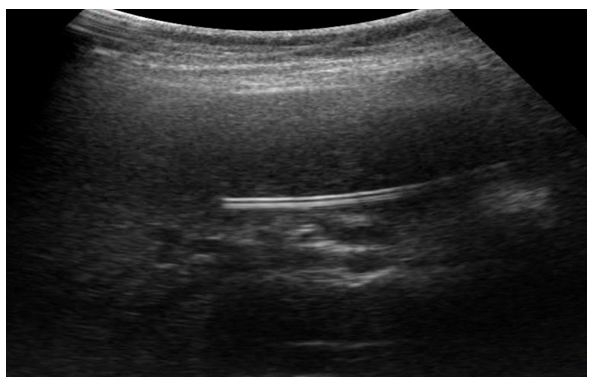

During the fourth stage, laparoscopic cholecystectomy was performed "from the neck".After laparoscopic cholecystectomy is completed, the paraumbilical trocar wound expands, and a 2-3 cm long skin incision is made with dissection of the subcutaneous tissue. At the end of the stage of isolating the round hepatic ligament and determining the umbilical vein, it is recanalized using a button probe, through which a subclavian catheter is inserted, up to the proximal sections of the portal vein, after which the catheter is fixed with a nylon thread.In the postoperative period, broad–spectrum antibiotics are injected into the bloodstream through an installed catheter: cephalosporini – ceftriaxone 1.0 + drugs that suppress pancreatic function - sandostatin 300-600 mg + antioxidants – mexidol 200 mg - for up to 7 days. As the indicators of endotoxemia, cytokine status and lipid peroxidation in the blood decrease and the patient's general condition improves (7-8 days), the catheter is removed.On the 3rd-5th day after administration of the drugs through the round hepatic ligament, patients with ACP showed a decrease in endotoxemia: the CRP level decreased to 115.1±12.8 mg/l, the number of leukocytes decreased to 6.3±0.8 x109/l, the LII values averaged 3.5±0.3 conl.units, MWS (medium molecular weight substances) - 674.25±40.5 micrograms/ml, lipid peroxidation - DC - 0.85±0.25 units, MDA - 2.2±0.3 micromol/l, cytokine profile - IL-6 - 103.4±9.2 pg/ml and TNF-α - 15.3±1.7 pg/ml. It should be noted that the above indicators after the usual, traditional intravenous and intramuscular administration of drugs in patients with ACP were significantly worse.This treatment strategy was successfully used in 11 patients with acute cholecystopancreatitis.In 10 (15.0%) cases of the main group, indications for urgent percutaneous drainage interventions were indicated due to the pronounced picture of ACP, there were indications for the imposition of a cholecystostomy under ultrasound control (Fig. 6, 7). | Figure 6. The stages of puncture with drainage of the gallbladder under ultrasound control |

| Figure 7. Ultrasound. Puncture with drainage of the gallbladder under ultrasound control |

It should be noted that after performing percutaneous drainage interventions on the gallbladder under ultrasound control, there is a noticeable improvement in the general condition of patients against the background of a decrease in endotoxemia.2-3 days after percutaneous drainage procedures on the gallbladder under visual ultrasound control, a decrease in the main indicators of endotoxemia was noted: the LII level averaged 2.39±0.9 units, the MWS values were 654.15±48.3 micrograms/ml, and the average leukocyte level was 6.5±0.4 x109/L.Puncture-draining surgical methods performed under ultrasound control subsequently made it possible to perform radical surgical interventions, i.e. laparoscopic cholecystectomy, after improving the general condition of patients.In patients of the control group, traditional open cholecystectomy and drainage of the subhepatic space were performed in 36 (75%) cases. In 12 (25%) cases, traditional cholecystectomy with open methods, choledocholithotomy, Robson drainage of the common bile duct, and drainage of the subhepatic space were performed.Based on our research, we have developed an algorithm for the diagnosis and surgical treatment of patients with ACP.The essence of the developed algorithm is that the more severe the condition of a patient with ACP, the less he needs to be subjected to surgical aggression. To do this, at the diagnostic stage, along with complaints, medical history, objective and clinical manifestations of the disease, it is necessary to analyze the results of laboratory and instrumental research methods. At the same time, the stages of the diagnostic algorithm should cover such important indicators as the levels of LPO products and cytokine profile. Radiation (ultrasound, CT) and endoscopic (FGDS) research methods play an important role in determining the choice of surgical treatment tactics.Naturally, with uncomplicated forms of ACP, preference should be given to LCE. ACP, accompanied by a picture of choledocholithiasis, taking into account the severity of the patients' condition, is subject to LERV, and in some cases, a two-stage tactic is preferable: EPST + LCE.A special contingent of patients are those at "high" risk, where surgical aggression is fraught with death. In such situations, we strongly recommend minimally invasive decompressive interventions (cholecyst/cholangiostomy) under ultrasound control. After the stabilization of the patients' condition, the second stage is performed by LCE.Table 2 shows an analysis of postoperative complications in the patients we observed.Table 2. Postoperative complications in patients with acute cholecystopancreatitis  |